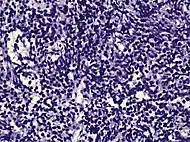

Small-cell carcinoma 0.3–2%[14][15][notes 1]

• Small blue cells with scant cytoplasm[1]

• High nucleus/cytoplasm ratio[1]

• "salt and pepper" chromatin[1]

• Nuclear molding[1]

• Necrosis of single cells, or geographic[1]

• Smearing artifacts[1]

Half of cases have usual acinar components[1]